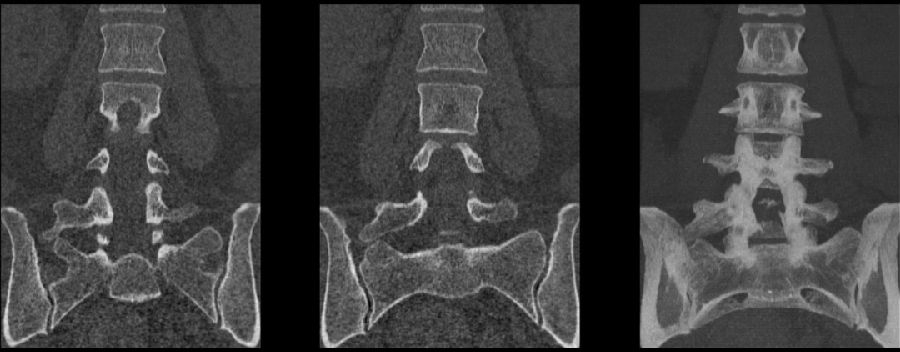

腰椎骶化及骶椎腰化均是椎骨发育的异常,腰椎骶化是指第五腰椎外型类似骶椎形态,并构成骶骨块的一部分,一侧或两侧横突肥大呈翼状,与骶骨发生融合或形成假关节。骶椎腰化是指第一骶椎演变成腰椎样形态,即第一骶骨从筋骨块中游离出来形成第6个腰椎。

如何在临床阅片准确判断是一个很重要的问题,这里介绍一个最准确的判断方法

这是一个最关键和准确的鉴定方法,国内著名骨放射学家杨世埙教授指导过,只要大家留意关注腰椎横突"三长/四翘/五宽",L3横突是最长的,L4横突是上翘的,L5横突最宽,特别用在胸椎腰化合并L5骶化的时候比较实用。

移行椎一般不引起症状,但是这种畸形可影响脊柱的稳定并逐渐产生症状,移行椎较正常椎体潜在着更多不稳。由于负重及运动不平衡,而引起腰痛。

它与腰骶部疼痛存在密切的相关性是不可忽视的并干扰诊断与之症状相近的其它疾病如椎间盘突出、致密性骨炎、强直性脊柱炎等等当然这其中有些疾病可以并存X线、CT检查在腰骶部移行椎的诊断中有重要意义不仅能对本病做出诊断并且有助于鉴别诊断。